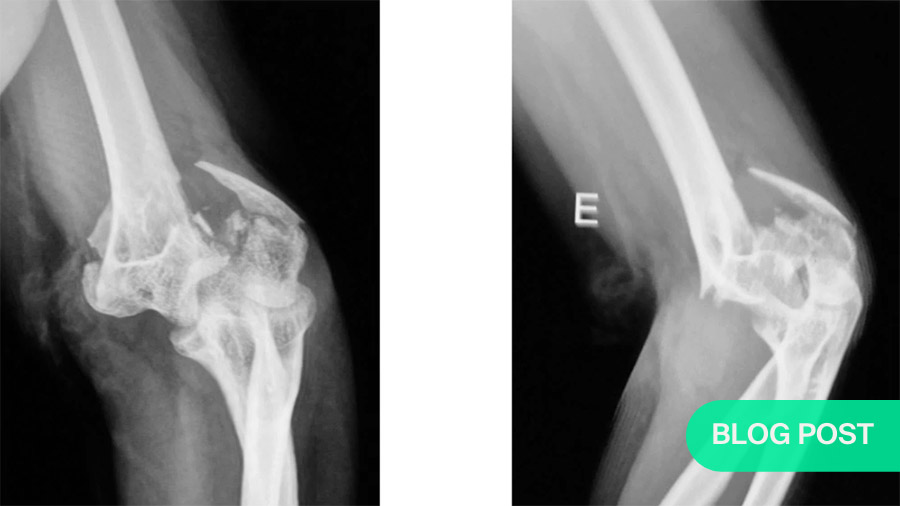

As an illustrative case, Labronici has chosen that of a 66-year-old woman with rheumatoid arthritis. She has suffered a fall with a closed fracture. Her neurovascular status is normal.

As the 3D CT image shows, the fractured elbow has no cartilage. Therefore, a total elbow arthroplasty is performed. Eighteen months post-operatively, the patient shows normal flexion and roughly 35 degrees of extension, with normal rotation of the radius and ulna.